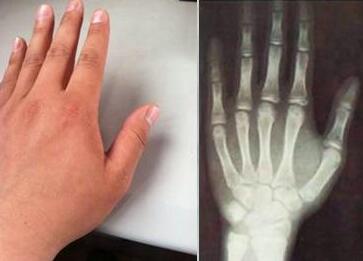

最近这几个月王女士总是经常发脾气,失眠多梦,厌食,喜冷。去医院检查,给予药物治疗。王女士发现自己的关节越来越疼痛了,手肿胀严重了。而且稍稍一动就疼的不得了。随后便来到我院接受治疗。 ...[详细]